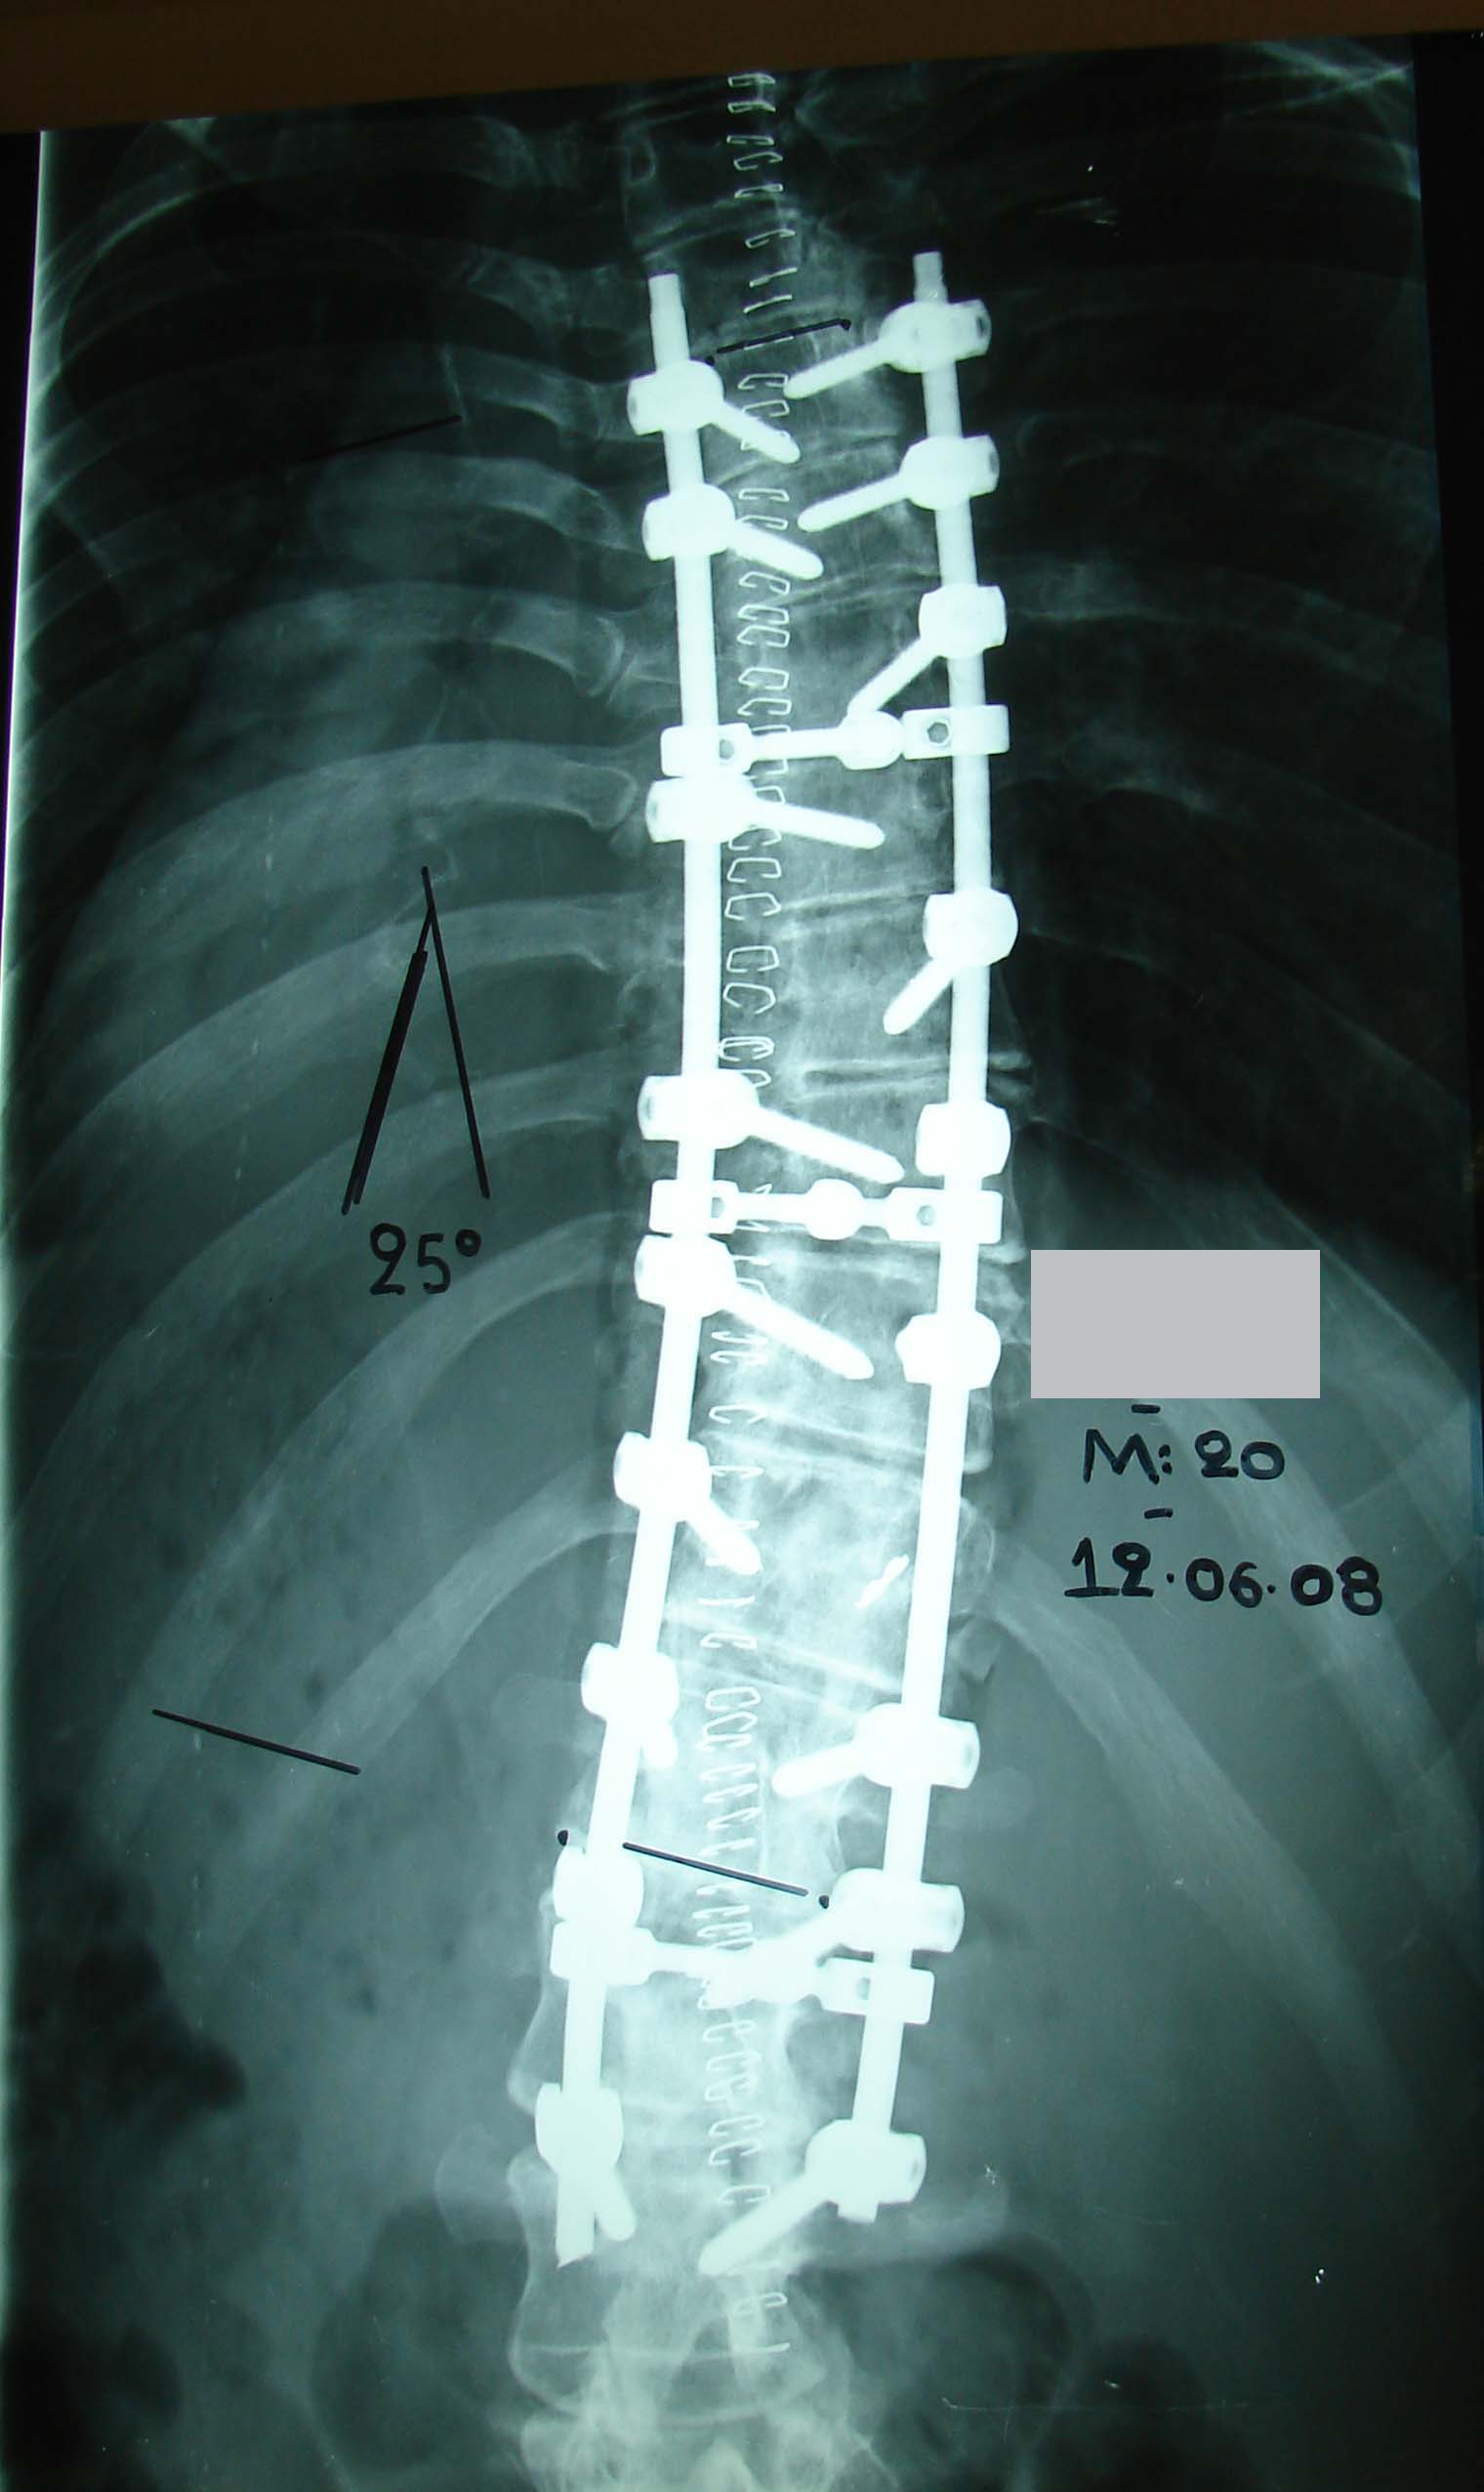

- α

- β

- γ

- δ

Εικόνα 4 (α,β,γ,δ) Ακτινογραφία προσθιοπισθία και πλαγία της Σπονδυλικής Στήλης. Παρατηρείται η ύπαρξη οργανικής σκολίωσης, δεξιάς θωρακο-οσφυϊκής (Θ7-Ο1 55ο) και αριστερής αντιρροπιστικής αυχενοθωρακικής και οσφυϊκής. Παρατηρείται ότι υφίσταται εξάλειψη της θωρακικής κύφωσης και οσφυϊκής λόρδωσης καθώς και της αυχενικής λόρδωσης.